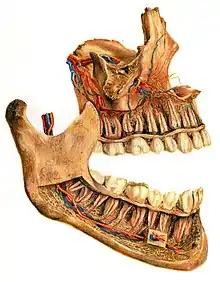

On the maxilla, the alveolar process is a ridge on the inferior surface, making up the thickest part of the bone. On the mandible it is a ridge on the superior surface. The structures hold the teeth and are encased by gums as part of the oral cavity.[11] Either alveolar process comprises cells, nerves, blood vessels, lymphatic vessels, and periosteum.[8] The alveolar crest terminates uniformly at about the neck of the teeth (within about 1 to 2 mm in a healthy specimen).[12][13]

The alveolar process proper encases the tooth sockets, and contains a lining of compact bone around the roots of the teeth, called the lamina dura.[8] This is attached by the periodontal ligament (PDL) to the root cementum.[8] Although the alveolar process is composed of compact bone, it may be called the cribriform plate because it contains numerous holes where Volkmann's canals pass from the alveolar bone into the PDL. The alveolar bone proper is also called bundle bone because Sharpey's fibres, part of the PDL, are inserted there. Sharpey's fibres in alveolar bone proper are inserted at a right angle (just as with the cemental surface); they are fewer in number, but thicker in diameter than those found in cementum.[8]

The supporting alveolar bone consists of both cortical (compact) bone and trabecular bone. The cortical bone consists of plates on the facial and lingual surfaces of the alveolar bone. These cortical plates are usually about 1.5 to 3 mm thick over posterior teeth, but the thickness is highly variable around anterior teeth.[13] The trabecular bone consists of cancellous bone that is located between the alveolar bone proper and the cortical plates.[14]

The radiographic integrity of the lamina dura is important in detecting pathological lesions. It appears uniformly radiopaque (or lighter).[8]